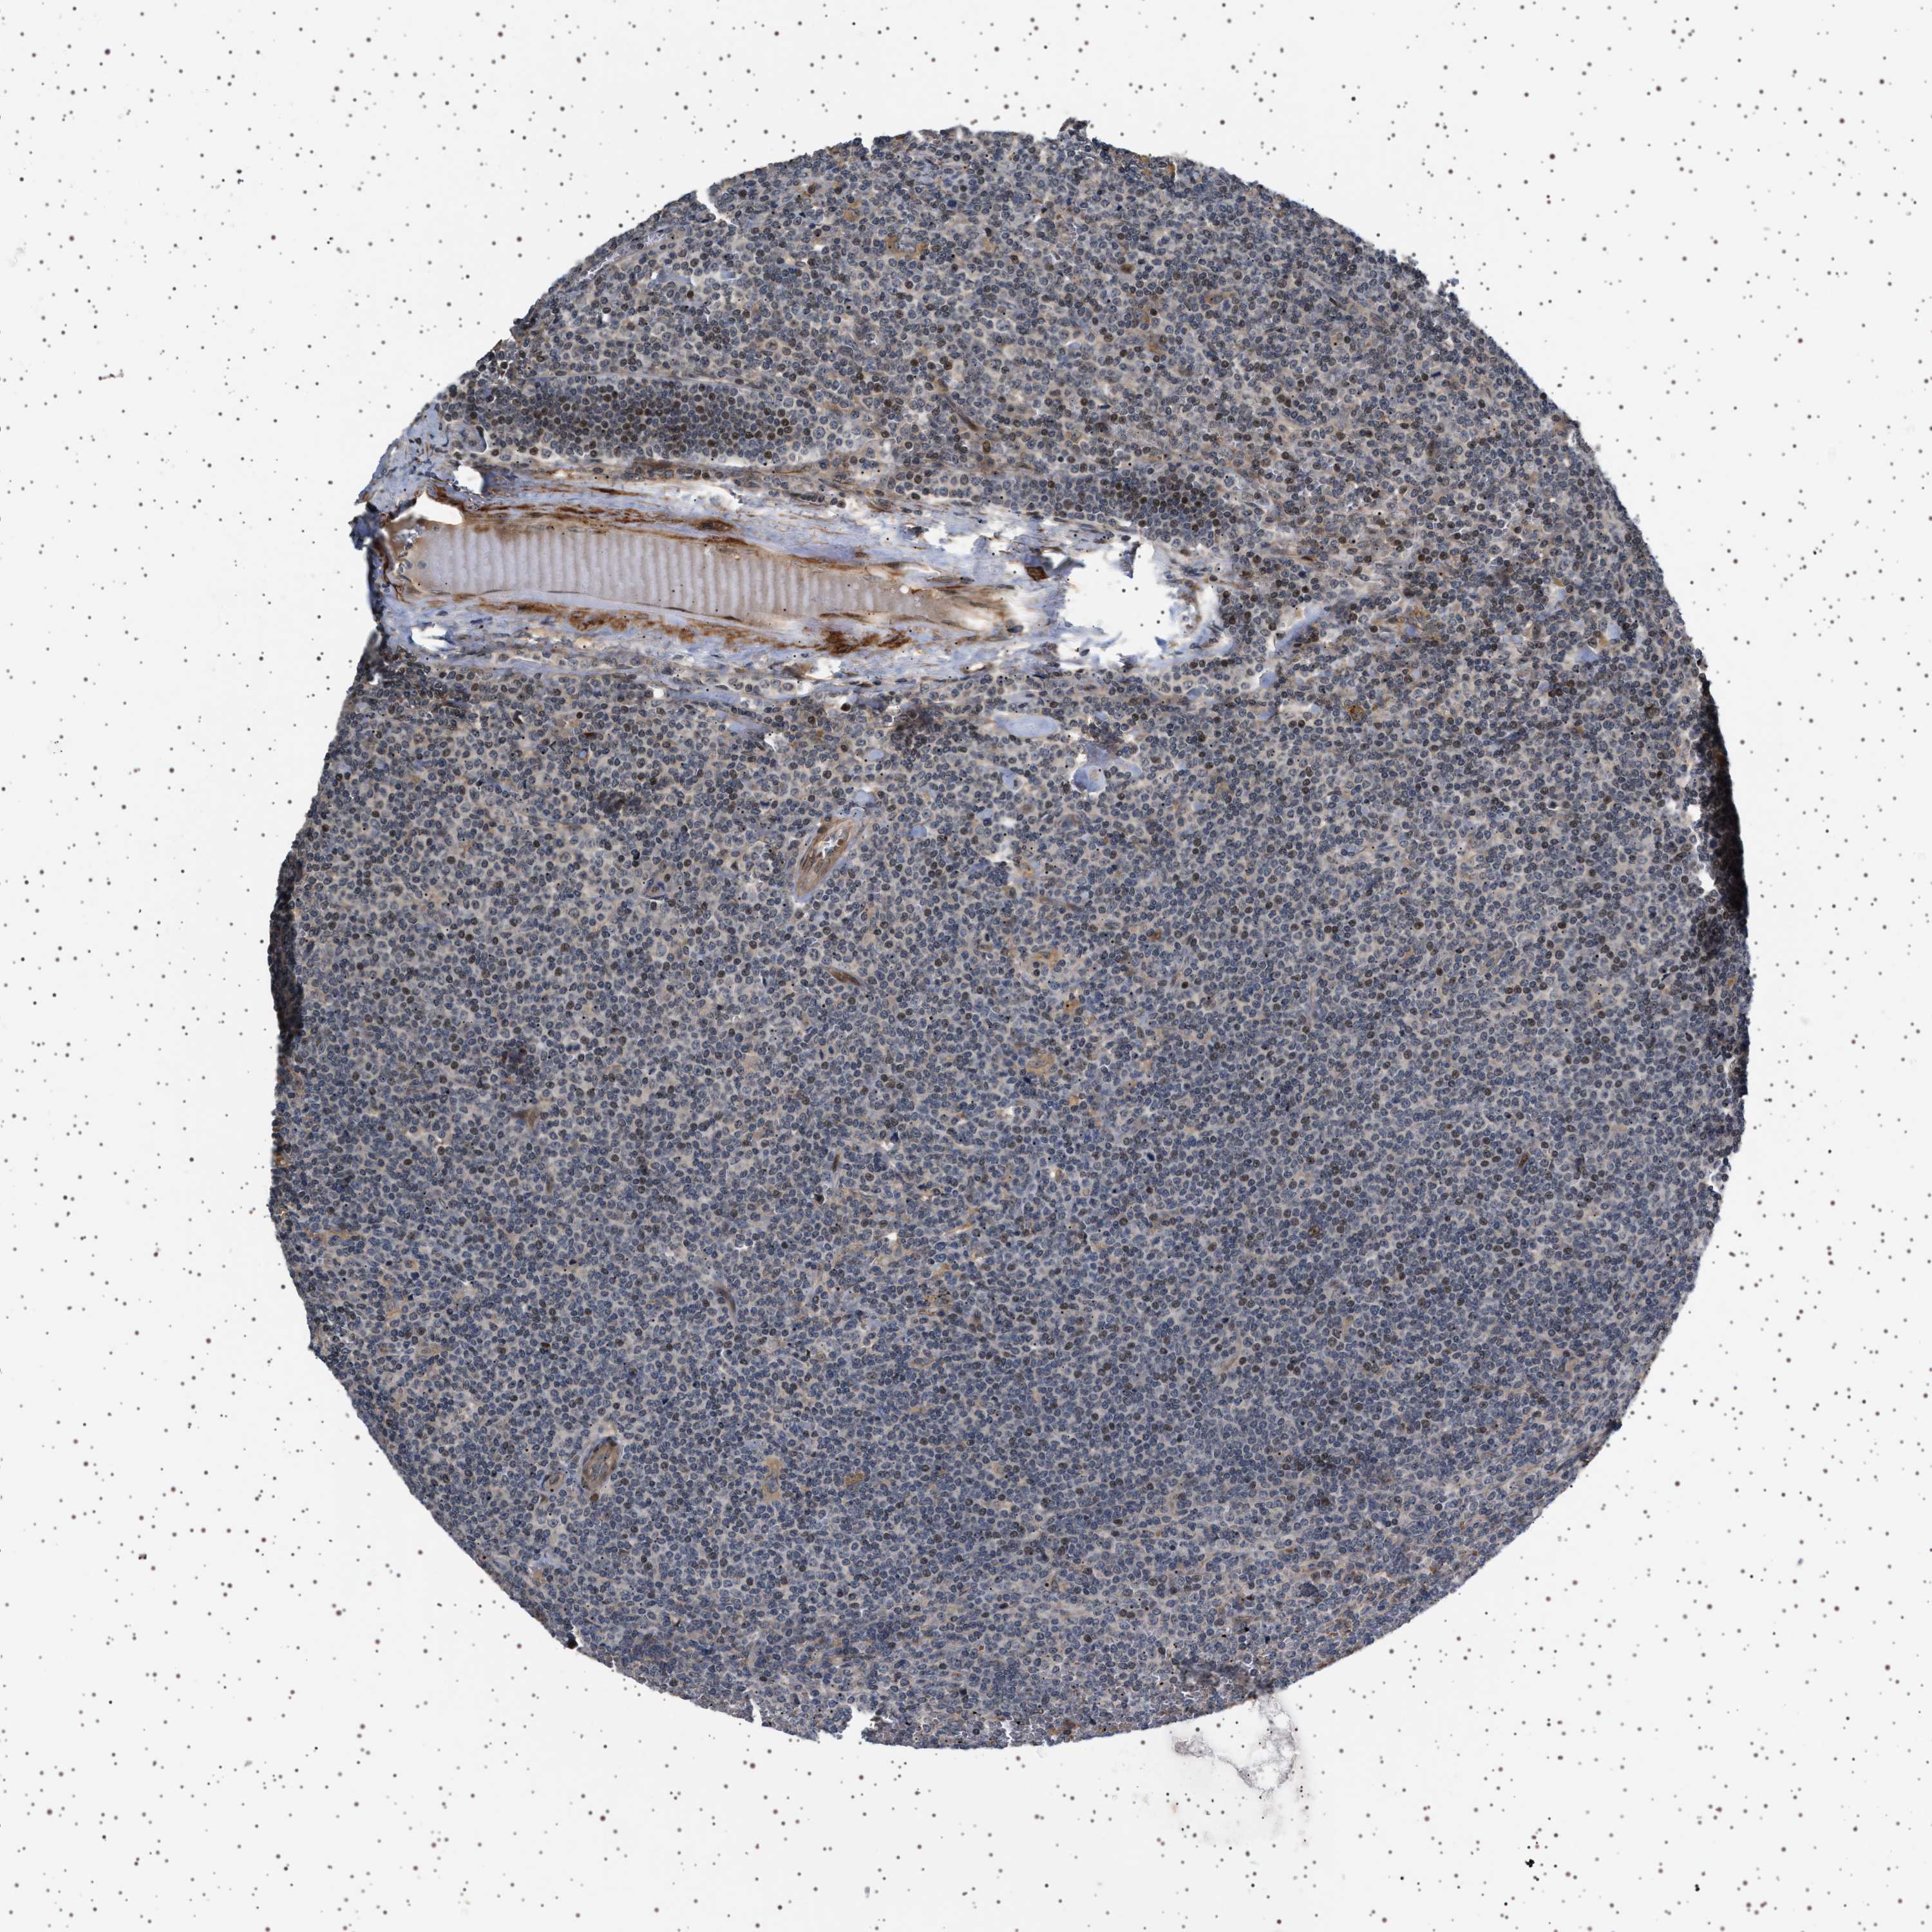

LYMPHOMA - Protein expressioni

A mouse-over function shows sample information and annotation data. Click on an image to view it in a full screen mode. Samples can be filtered based on level of antibody staining by selecting one or several of the following categories: high, medium, low and not detected. The assay and annotation is described here.

Each image is clickable and will lead to virtual microscopy that enables deeper exploration of all samples and also displays staining intensity scores, fraction scores and subcellular localization as well as patient and tissue information for each sample.

Antibody HPA018493

Hodgkin's disease, NOS

Malignant lymphoma, non-Hodgkin's type, High grade

Malignant lymphoma, non-Hodgkin's type, Low grade